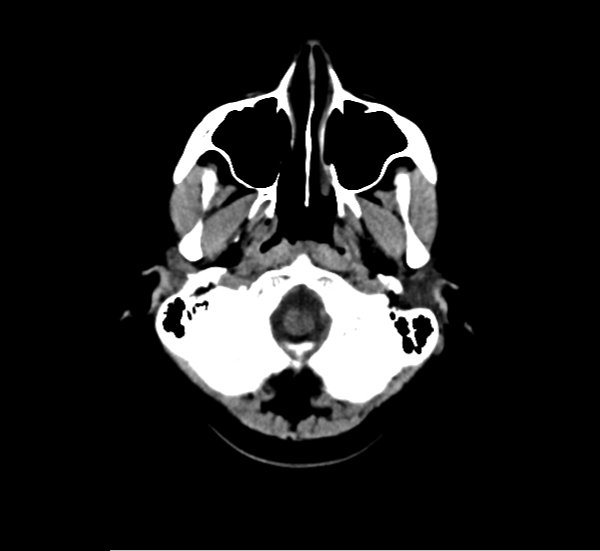

CT Brain Anatomy